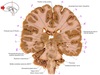

37

a

body of fornix

38

b

Septum pellucidum

39

c

Body of corpus callosum

40

d

Body of lateral ventricle

41

e

Body of caudate nucleus

42

f

Posterior limb of internal capsule

43

g

Putamen

44

h

Tail of caudate nucleus

45

i

Interpeduncular fossa

46

j

interthalamic adhesion

47

k

Inferior horn of lateral ventricle

48

L

Hypothalamus

49

m

Corona radiata